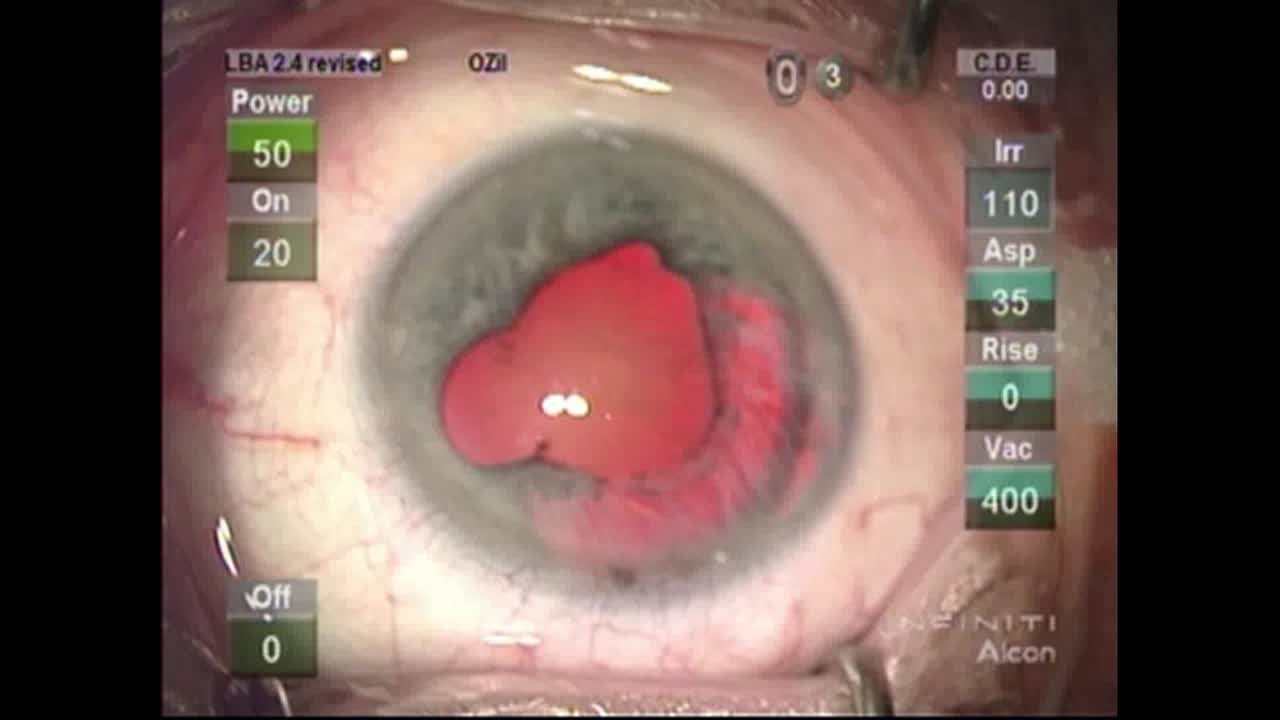

Morgagnian Cataract

Lisa Brothers Arbisser, MD